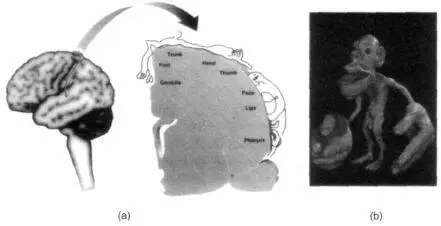

Of the many strange images that have remained with me from my medical school days, perhaps none is more vivid than that of the deformed little man you see in Figure 2.1 draped across the surface of the cerebral cortex — the so-called Penfield homunculus. The homunculus is the artist’s whimsical depiction of the manner in which different points on the body surface are mapped onto the surface of the brain — the grotesquely deformed features are an attempt to indicate that certain body parts such as the lips and tongue are grossly overrepresented.

Among other things, Penfield found a narrow strip running from top to bottom down both sides of the brain where his electrode produced sensations localized in various parts of the body. Up at the top of the brain, in the crevice that separates the two hemispheres, electrical stimulation elicited sensations in the genitals. Nearby stimuli evoked sensations in the feet. As Penfield followed this strip down from the top of the brain, he discovered areas that receive sensations from the legs and trunk, from the hand (a large region with a very prominent representation of the thumb), the face, the lips and finally the thorax and voicebox. This “sensory homunculus”, as it is now called, forms a greatly distorted representation of the body on the surface of the brain, with the parts that are particularly important taking up disproportionately large areas. For example, the area involved with the lips or with the fingers takes up as much space as the area involved with the entire trunk of the body. This is presumably because your lips and fingers are highly sensitive to touch and are capable of very fine discrimination, whereas your trunk is considerably less sensitive, requiring less cortical space. For the most part, the map is orderly though upside down: The foot is represented at the top and the outstretched arms are at the bottom. However, upon close examination, you will see that the map is not entirely continuous. The face is not near the neck, where it should be, but is below the hand. The genitals, instead of being between the thighs, are located below the foot. 4

Figure 2.1 (a) The representation of the body surface on the surface of the human brain (as discovered by Wilder Penfield) behind the central sulcus. There are many such maps, but for clarity only one is shown here.

The homunculus (“little man”) is upside down for the most part, and his feet are tucked onto the medial surface (inner surface) of the parietal lobe near the very top, whereas the face is down near the bottom of the outer surface. The face and hand occupy a disproportionately large share of the map. Notice, also that the face area is below the hand area instead of being where it should — near the neck and that the genitals are represented below the foot. Could this provide an anatomical explanation of foot fetishes? (b) A whimsical three-dimensional model of the Penfield homunculus — the little man in the brain depicting the representation of body parts. Notice the gross overrepresentation of mouth and hands. Reprinted with permission from the British Museum, London.